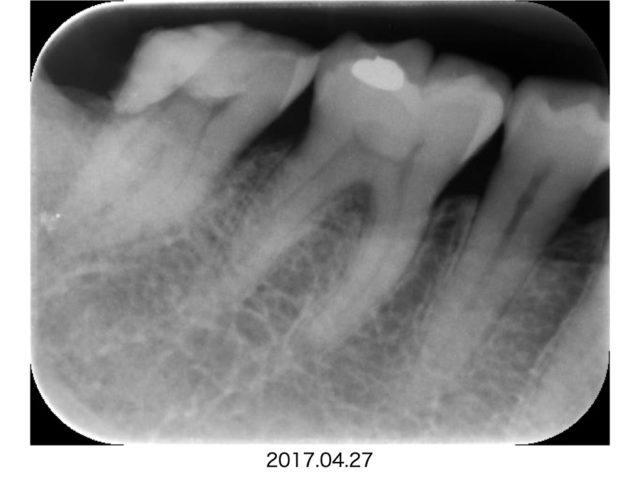

今回の症例は親知らずとの間にできたむし歯です。

親知らずが右下7番にぴったりくっついていて、むし歯の疑いがあります。

そのままではむし歯は確認しづらく、親知らずの抜歯を勧めていました。

根管充填後のx線写真でも歯槽骨の透過像なく安定しています。